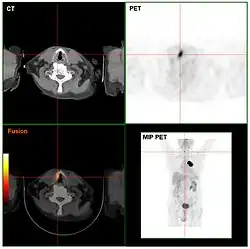

Tomography

Computed tomography (CT) and positron emission tomography (PET) scans are similar to MRI, but rely on different imaging techniques (X-rays and ionizing radiation, respectively). A variation of CT known as contrast CT also requires the subject to take in a contrast medium called a radiocontrast (typically by oral consumption, enema, or injection). Positive radiocontrast agents such as barium sulfate increase the body's X-ray attenuation, causing the tissue containing them to appear whiter in the X-ray image. Meanwhile, negative agents such as carbon dioxide gas allow X-rays to pass through them easily, causing the tissues containing them to appear darker.[49]

Like magnetic resonance imaging, CT scans use numerous methods to display and measure data, including sequential CT (where the CT table steps from location to location), spiral CT (where the entire X-ray tube is spun around the subject), and electron beam tomography (where only the electron paths are spun using deflection coils). PET scanners don’t have quite as much hardware variation and instead use different radiotracers depending on what the imaging target is. Note that radiotracers are distinct from radiocontrasts; the former relies on radioactive decay to trace its path while the latter is absorbed into specific tissue and affects that tissue's X-ray attenuation. Because these methods are not mutually exclusive, PET and CT can be performed simultaneously using PET-CT scanners, which are used for the majority of modern PET scans.[50]

Either or both of these methods can be used in conjunction with maximum intensity projection (MIP) to convert the scan data into a 3D image. This can be difficult to accomplish due to artifacts created by respiration and bloodflow, which can appear as abnormalities to an untrained eye; however, it's possible to distinguish these artifacts from real disease so long as careful attention is paid to them.[51] When done well, CT and PET scans taken with MIP are excellent for identifying small abnormal tissue growths, especially in the lungs. Scans taken with MIP for this purpose tend to have higher significance than averaged images created with traditional CT.[52]

MIP imaging is also used with magnetic resonance angiography, and research has indicated that it could feasibly be used with MRI.[53] At least one study has shown that MIP MRI actually significantly outperforms single-slice MRI when used by neural networks to classify lesions based on malignancy.[54]